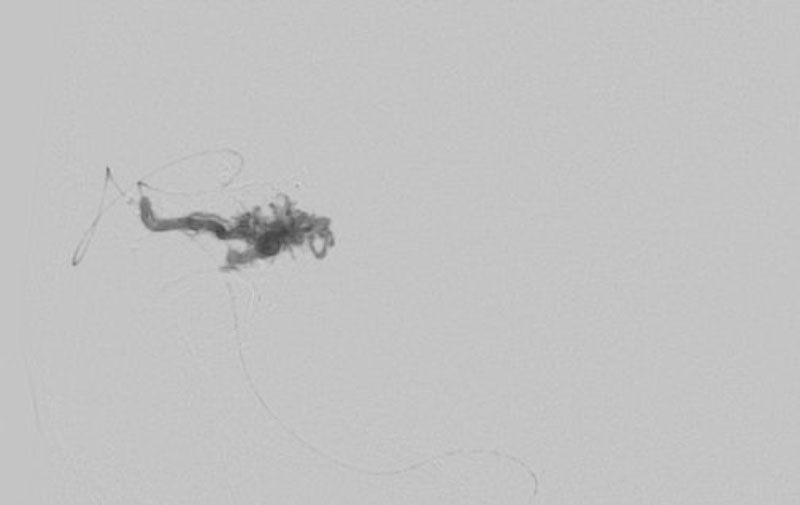

No.1620 手術中